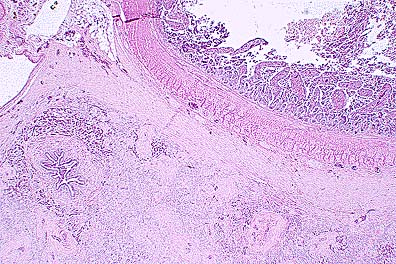

Necrotizing enteritis and ulceration in a red-tailed boa constrictor with zygomycosis and concurrent boid inclusion disease. (HE, 40X, 63K)

Pleomorphic fungal hyphae within the ulcerated areas of the enteric mucosa which have non-parallel walls, range up to 20 microns in diameter, are pauciseptate, and stain well with HE - all characteristics of a zygomycete. Further speciation is not possible based on examination of this fungus in tissue section. (HE, 400X, 50K)

Numerous round cytoplasmic inclusions with enteric mucosal epithelial cells, which are characteristic findings in boid inclusion disease. Inclusions were also seen in lymphocytes and cells of the myenteric plexus. (HE, 400X, 32K)

Contributor's Diagnosis and Comments: 1. Necrotizing enteritis, heterophilic and granulomatous, moderate, focal, with intra-lesional fungal hyphae and yeast forms - presumptive etiology: Aspergillus clavatus, Trichosporon beigelii.

2. Intra-cytoplasmic eosinophilic inclusion bodies in most cell types - Boid inclusion body disease.

Inclusion body disease (IBD) affects various species of boid snakes and usually manifests as progressive debilitation, anorexia, weight loss, regurgitation, and neurologic signs. The presence of the typical, well-defined intracytoplasmic eosinophilic inclusion bodies is often associated with cellular degeneration in various tissues, most commonly in the CNS, where a non-suppurative encephalomyelitis can also be observed. Various secondary infections are frequently associated with IBD, such as pneumonia and nephritis. In this boa, encephalitis was not noted, although inclusions were numerous in the brain, and were associated with degeneration. The animal also had a mycotic enteritis affecting a focal segment of distal small intestine. The morphology of the fungal elements (pleomorphic hyphae, yeast forms) was compatible with both the Aspergillus clavatus and Trichosporon beigelii organisms obtained by fungal culture of the intestinal contents. The boa probably developed fungal enteritis from the changes in gut flora induced by prolonged antibiotic treatment; IBD may have been a predisposing factor. Electron microscopy of liver tissue revealed that the inclusions contained granular homogenous osmiophilic material. Lined around the periphery, and occasionally inside the inclusions were numerous clathrin-coated pinocytotic vesicles. A few particles consistent with type C retroviruses, measuring 95-110 nm, were observed in the intercellular spaces, sometimes budding from the cell membrane. The particles were similar to those previously reported in snakes with IBD (see reference).

AFIP Diagnosis: 1. Intestine: Enteritis, ulcerative, necrotizing, granulomatous, multifocal, severe, with fungal hyphae, red-tailed boa constrictor (Boa constrictor), reptile, etiology consistent with a zygomycete. 2. Intestinal epithelium; lymphocytes; intestinal ganglion cells of myenteric plexi: Eosinophilic intracytoplasmic inclusion bodies.

Conference Note: The inclusions in submitted tissues are eosinophilic to amphophilic, range up to 10 microns in diameter, and did not appear to be associated with degenerative or inflammatory changes. The morphologic features of the fungus are consistent with the those of the Class Zygomycetes and not with Aspergillus or Trichosporon spp. These features include broad, thin-walled, infrequently septate, pleomorphic hyphae that range from about 5 to 20 m in width and irrgeular right angle branches. The fact that the hyphae stain well with H&E is also characteristic of a zygomycete.

Inclusion body disease of boid snakes has been recognized for over 20 years in private and zoological collections in the United States. The disease affects only snakes of the Family Boidae including both boa constrictors and pythons. The disease is characterized by the formation of intracytoplasmic inclusions in the epithelial cells of all major organs and neurons in the central nervous system. Clinical symptoms include head tremors, disorientation, incoordination, and regurgitation. Ultrastructurally, a type C retrovirus has been associated with the lesions. The presence of a retrovirus is supported by demonstration of reverse transcriptase activity in the plasma and within the supernatant from primary kidney cell cultures of affected snakes.

Major histologic lesions include a nonsuppurative meningoencephalitis with neuronal degeneration, gliosis, and demyelinization. Intracytoplasmic inclusions are noted within degenerating neurons of the gray matter and ependymal cells. Inflammation in the central nervous system is more severe in pythons; however, intracytoplasmic inclusions are more numerous in boa constrictors. In the experience of pathologists at the National Zoological Park, Washington D.C., inclusion body disease has been found not only as a primary disease but also in association with secondary infections or as an incidental finding. In fact, many lesions within visceral organs of affected snakes have been attributed to secondary infections.